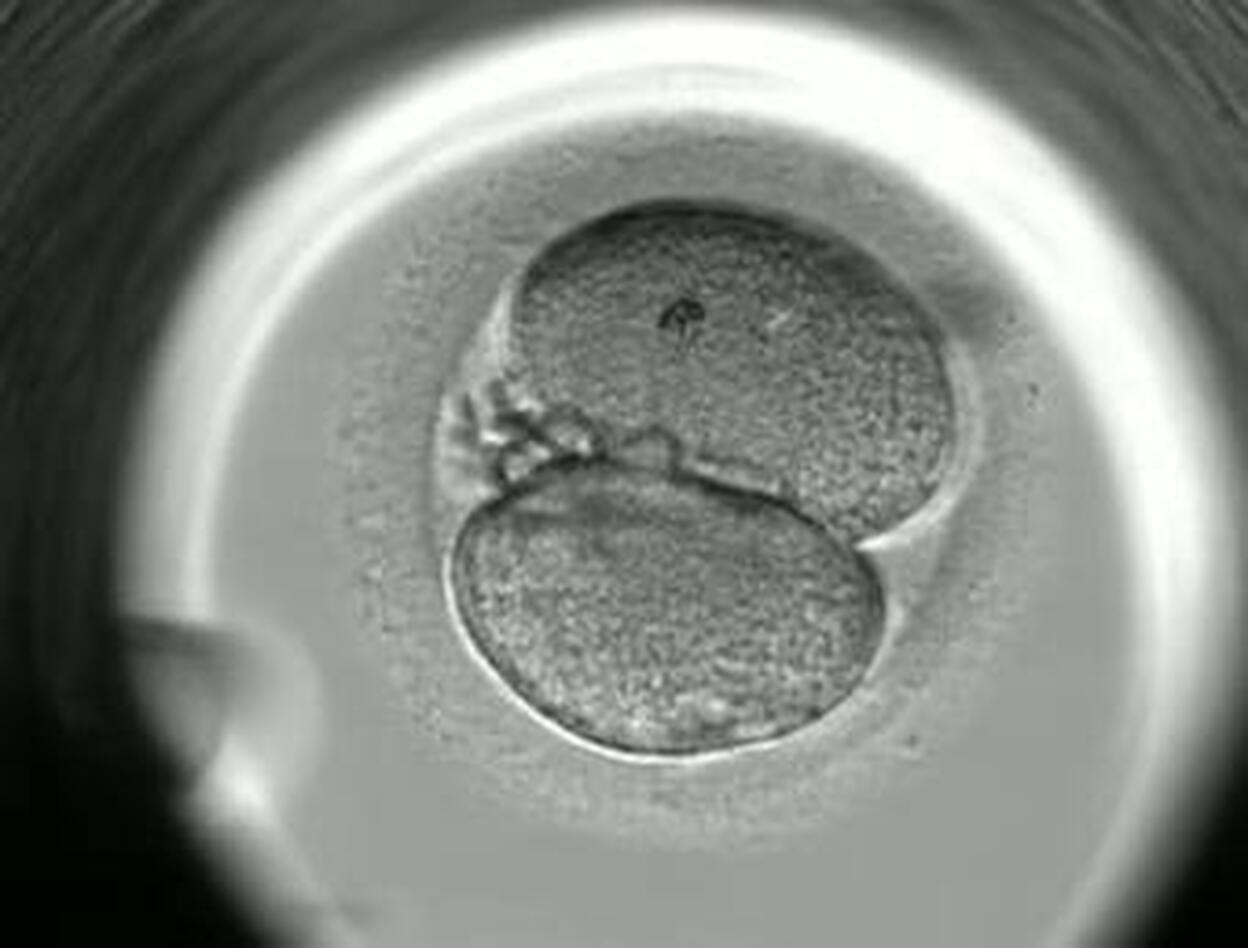

El Embryoscope es una innovadora tecnología que está revolucionando la medicina embrionaria. Se trata de un avanzado incubador que permite observar al embrión minuto a minuto desde el momento de la fecundación In Vitro hasta el de la transferencia al útero. Tiene una peculiaridad especial: incorpora una cámara que continuamente captura imágenes del desarrollo embrionario y se comprimen en una película de unos 30 segundos. En este vídeo, cedido por IVI Las Palmas, se observa la evolución del desarrollo del embrión en sus primeros cinco días de vida.